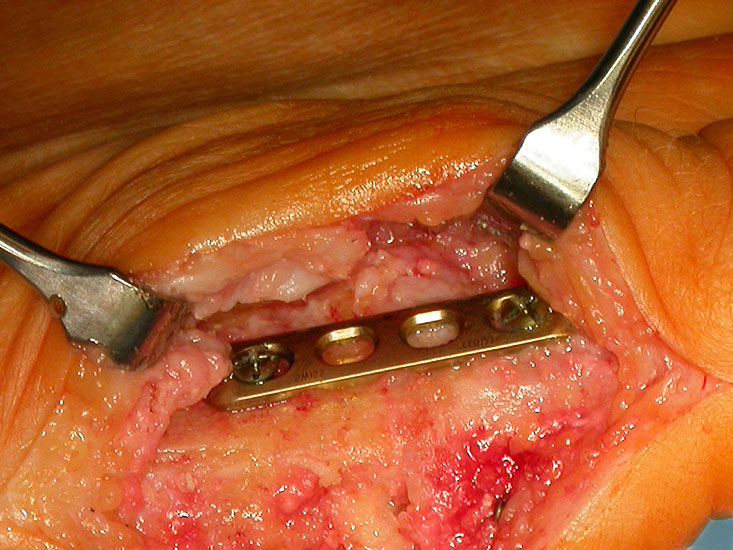

Der Zugang bei der Arthrodese mit den konischen Fräsen erfolgt von dorsal, da das Gelenk dadurch besser exponiert werden kann. Die Streckersehnen werden nach lateral weggehalten. Das Grundglied wird nach der Osteophytenabtragung und der Kapsulolyse scharnierartig nach plantar gekippt. Zentral in die Knochen eingebrachte Führungskirschnerdrähte ermöglichen das Fräsen und Abrunden des Kopfes und das Modellieren der kongruenten Grube an der Zehenbasis. Die Definition der idealen Zehenposition erfolgt wiederum mit einer flachen Unterlage. Diverse Fixationstechniken sind beschrieben 3940. Wir fixieren die Arthrodese mit einer Platte 2,0 (Abb. 9-12) oder 2,7, da mit den kleinen Implantatdimensionen bei Bedarf mehrere unterschiedliche Schraubenpositionen möglich sind.